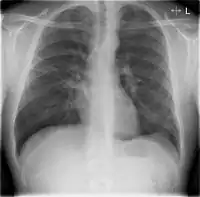

Chest X-rays and X-ray computed tomography (CT) can reveal areas of opacity (seen as white), indicating consolidation.[13] CAP does not always appear on x-rays, sometimes because the disease is in its initial stages or involves a part of the lung not clearly visible on x-ray. In some cases, chest CT can reveal pneumonia not seen on x-rays. However, congestive heart failure or other types of lung damage can mimic CAP on x-ray.[15]

When signs of pneumonia are discovered during evaluation, chest X-rays and examination of the blood and sputum for infectious microorganisms may be done to support a diagnosis of CAP. The diagnostic tools employed will depend on the severity of illness, local practices and concern about complications of the infection. All patients with CAP should have their blood oxygen monitored with pulse oximetry. In some cases, arterial blood gas analysis may be required to determine the amount of oxygen in the blood. A complete blood count (CBC) may reveal extra white blood cells, indicating infection.

Ceftriaxone and azithromycin are often used to treat community acquired pneumonia, which usually present with a few days of cough, fever, and shortness of breath. Chest x-ray typically reveals a lobar infiltrate (rather than diffuse).[19]